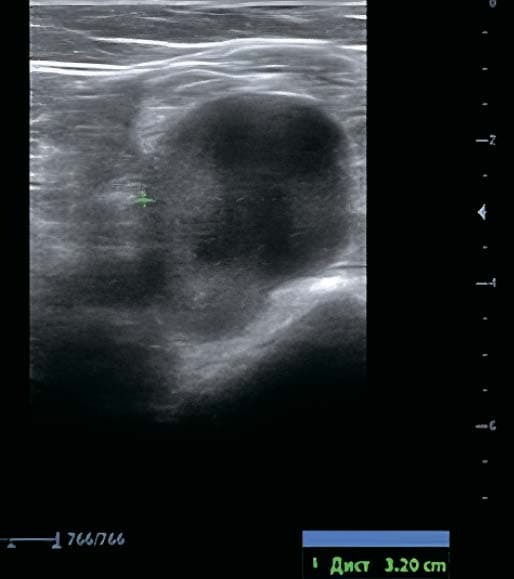

paiicyifc5Рисунок 3. Аневризма подколенной вены диаметром 32×42 мм на УЗИ.По данным УЗИ выявлена аневризма проксимальной части подколенной вены диаметром 32×42 мм, с турбулентным кровотоком в полости аневризмы и эффектом спонтанного контрастирования (см. рис. 3).